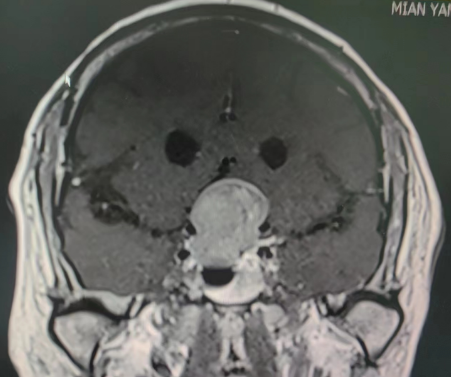

术后影像学资料

由于准备充分,郭大爷的手术非常成功。手术后他思维清醒,复查结果显示鞍区肿瘤切除干净,没有残留。术后郭大爷的左眼视力明显好转,几乎失明的右眼也能模糊的辨别物体。据了解,这样的鞍区垂体肿瘤在神经外科十分常见,由于肿瘤生长缓慢,患者多在病变的发展过程中未给予重视,当出现视力严重障碍及内分泌障碍时才发现。传统的开颅手术方式切除肿瘤术中出血多,病人手术时间长,常常加重患者的手术风险和术后并发症。目前随着神经内镜的普及和我院4K神经内镜使用,手术时间缩短、出血更少、风险更小,为鞍区患者的肿瘤手术治疗更好保驾护航。